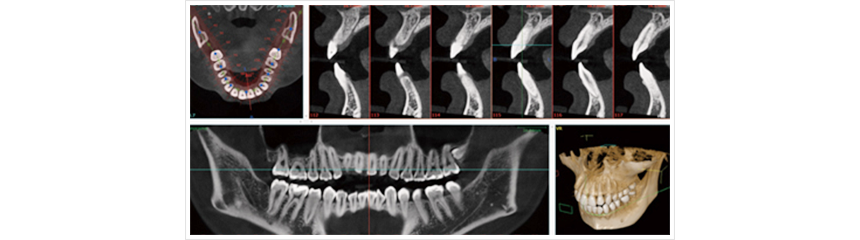

歯科用CTを完備しています

顎の骨の厚み、どこにインプラントを入れればいいかを調べます。

顎の中には様々な神経が存在します。

適切な位置にインプラントを埋入するために、CTによる3D画像で検査をしていきます。